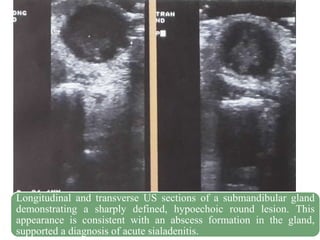

Longitudinal and transverse US sections of a submandibular gland

demonstrating a sharply defined, hypoechoic round lesion. This

appearance is consistent with an abscess formation in the gland,

supported a diagnosis of acute sialadenitis.

30 Longitudinal and transverseUS sections of a submandibular gland demonstrating a sharply defined, hypoechoic round lesion. This appearance is consistent with an abscess formation in the gland, supported a diagnosis of acute sialadenitis.